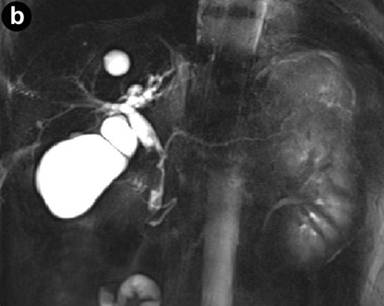

MR imaging was successively performed to evaluate and characterize the nature of the biliary stenosis by acquiring axial and coronal T1- and T2-weighted with/without fat saturation images integrated with MRCP T2-weighted hydro-cholangiographic sequences. In particular, the patient received 900 mL of superparamagnetic oral contrast material (Lumirem®, Guerbet, Paris, France) 20 min before the study. Post-contrast acquisition was performed after the intravenous administration of gadolinium diethylenetriamine pentaacetic acid (DTPA) in a volume of 20 mL with 2 mL/s acquiring T1 fast-field echo short-time inversion recovery (FFE-STIR) images. In particular, cross-sectional T1- and T2-weighted and MR cholangiography sequences showed dilatation of the biliary tree including the intrahepatic ducts, primarily of the left hepatic lobe and the common hepatic duct. Furthermore, MR images showed a lengthy stricture with luminal flow-signal preserved, irregular margins as well as abrupt and asymmetric narrowing in the middle third and intra-pancreatic segment of the common bile duct (Figure 1). A solid lesion along the common bile duct, at same level of the stricture, appearing as circumferential wall-thickening with a firm component projecting into the duct lumen, was also detected (Figure 2); after the administration of contrast medium, the lesion did not show significant enhancement in the arterial phase; however, late-phase images showed non-homogeneous enhancement (Figure 3). There was no evidence of positive lymph nodes or metastatic disease; the characteristics of the MR images were suggestive of a malignant primary stenosis probably by extra-hepatic cholangiocarcinoma. Furthermore, MR views demonstrated mild enlargement of the pancreas associated with a non-homogeneous signal intensity of the pancreatic tissue due to the presence of a hypointense nodule (Figure 3). A second ERCP examination was subsequently performed, which revealed a stricture immediately above and at the level of the intra-pancreatic common bile duct and the biliary stent was removed; brush cytology did not reveal atypical cells and the final report was not indicative of malignancy.

Figure 2. Cross-sectional T2-weighted fat-suppressed images. Axial T2-weighted turbo spin eco short-time inversion recovery (STIR) sequences show a circumferential wall-thickening of the common bile duct with a firm component projecting into the lumen. |